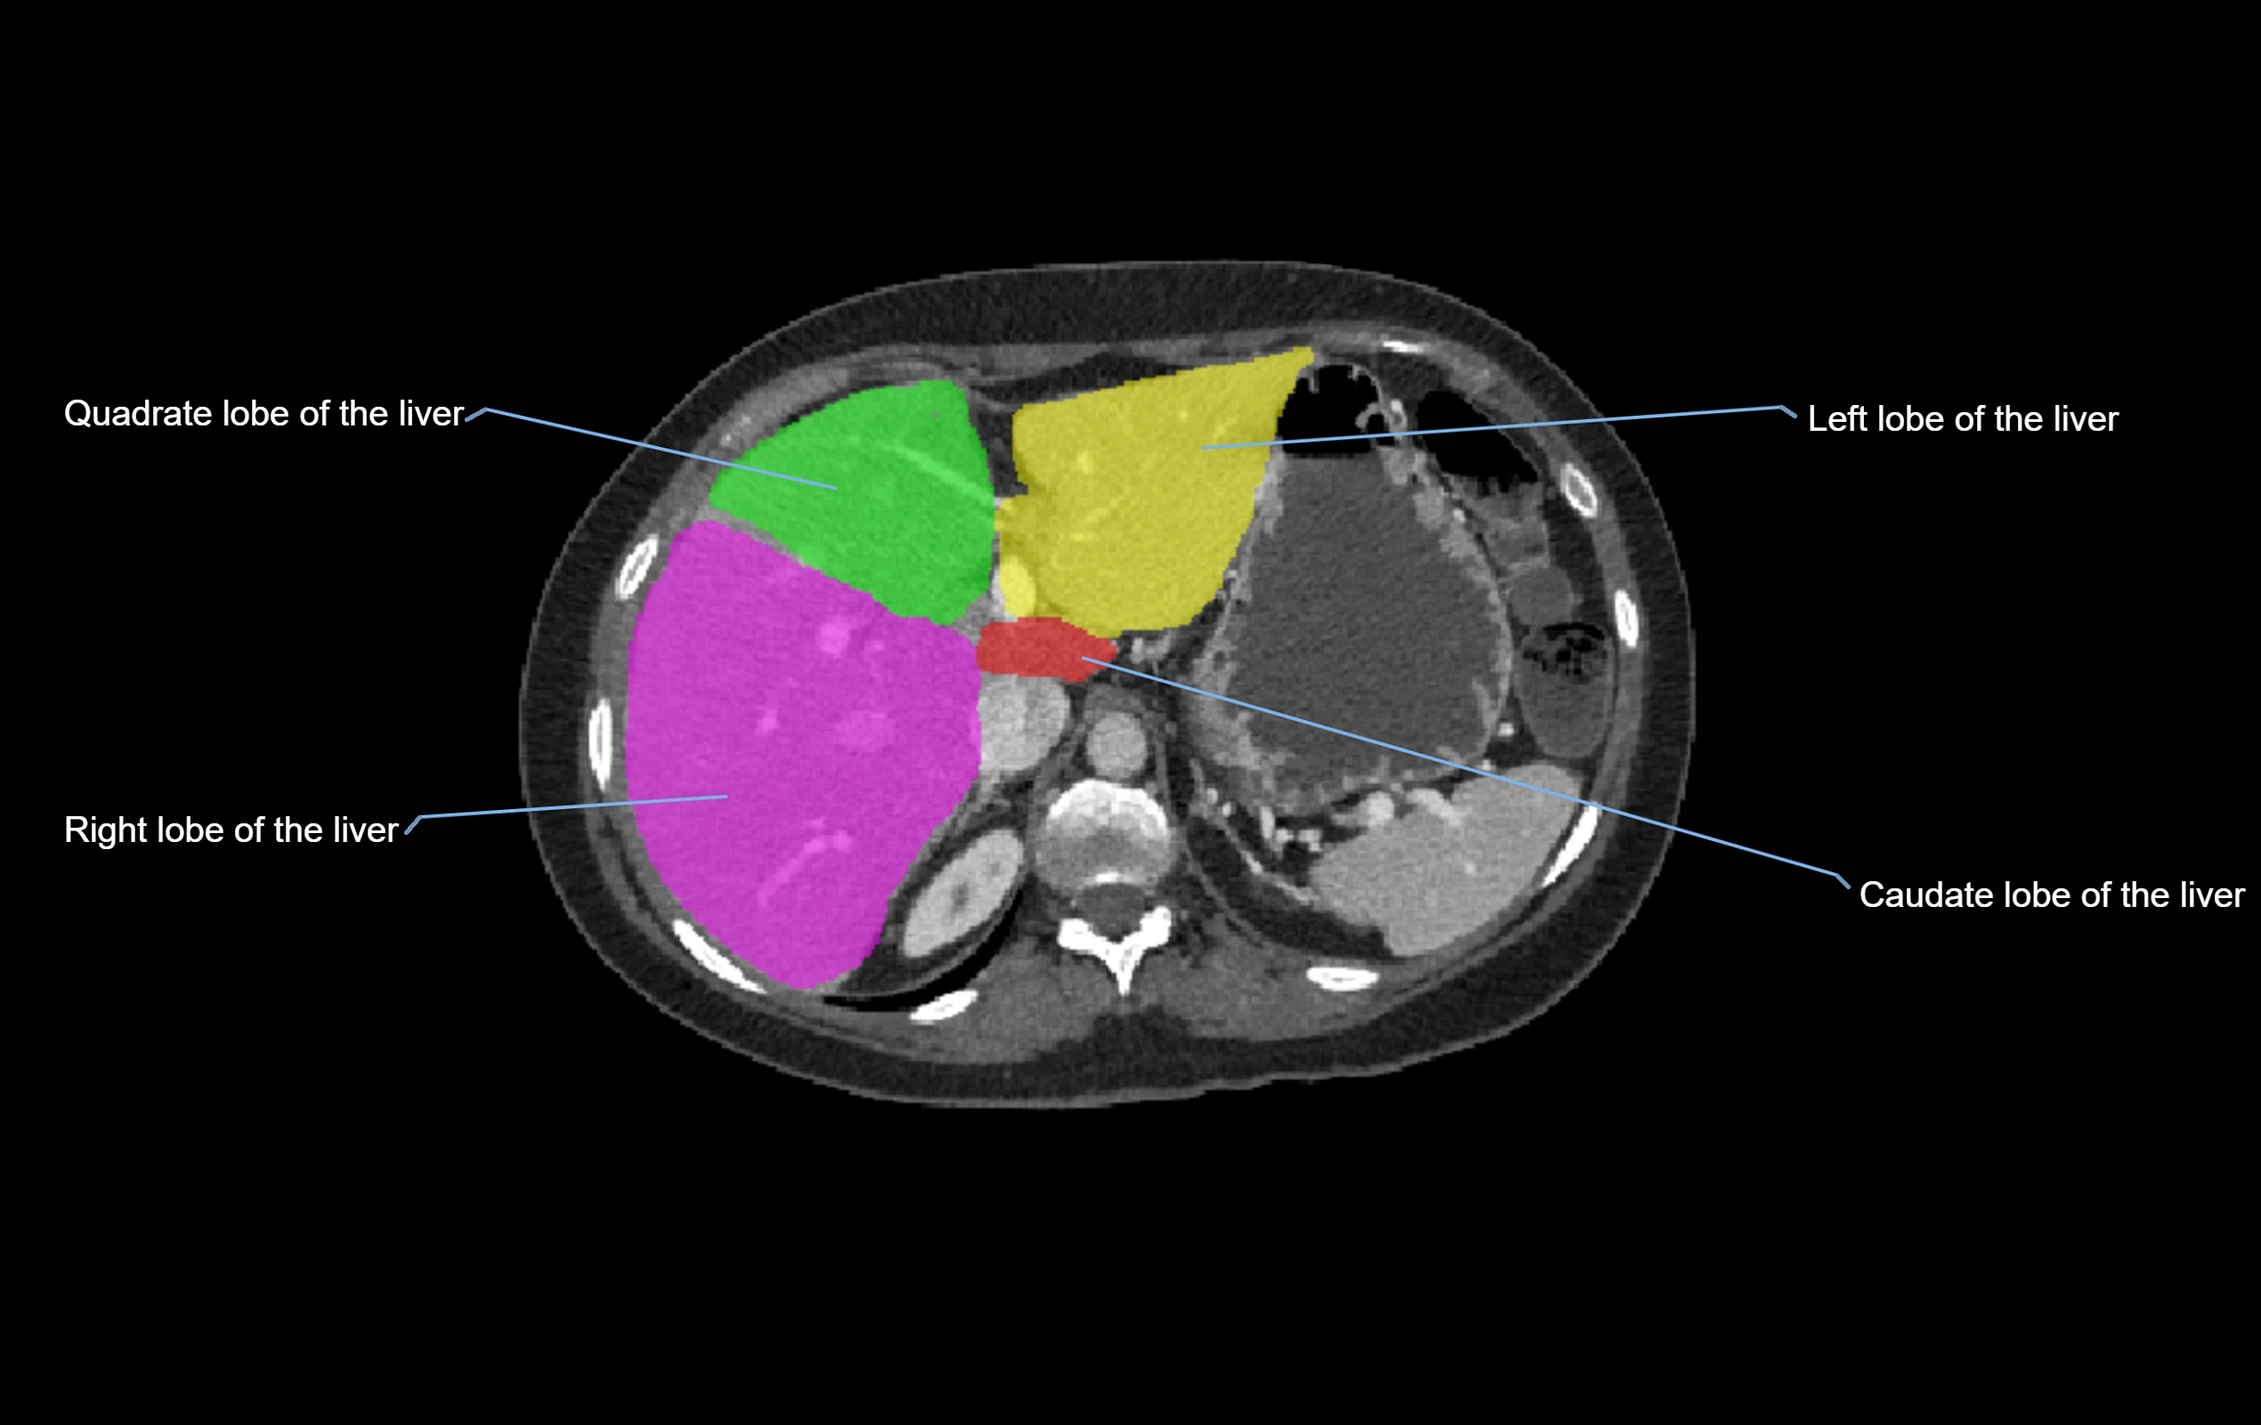

CT Image

image